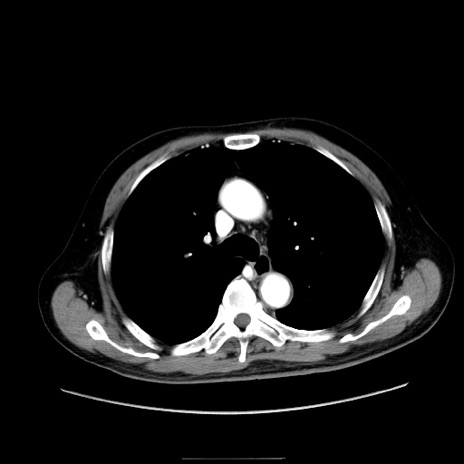

症例30(横断像)

【症例】80歳代男性

【主訴】臍周囲痛

【現病歴】約6時間前から臍下部痛が出現。次第に腹部膨隆・背部痛も生じてきたため来院。背部痛の場所は変化しない。

【身体所見】意識清明、BT 36.3℃、BP  131/87mmHg、P 87bpm、SpO2 100%(RA)、臍周囲自発痛・圧痛あり、反跳痛なし、自発痛部位に一致して板状硬あり、腹部膨隆、腸雑音減弱、CVA tenderness両側陰性。